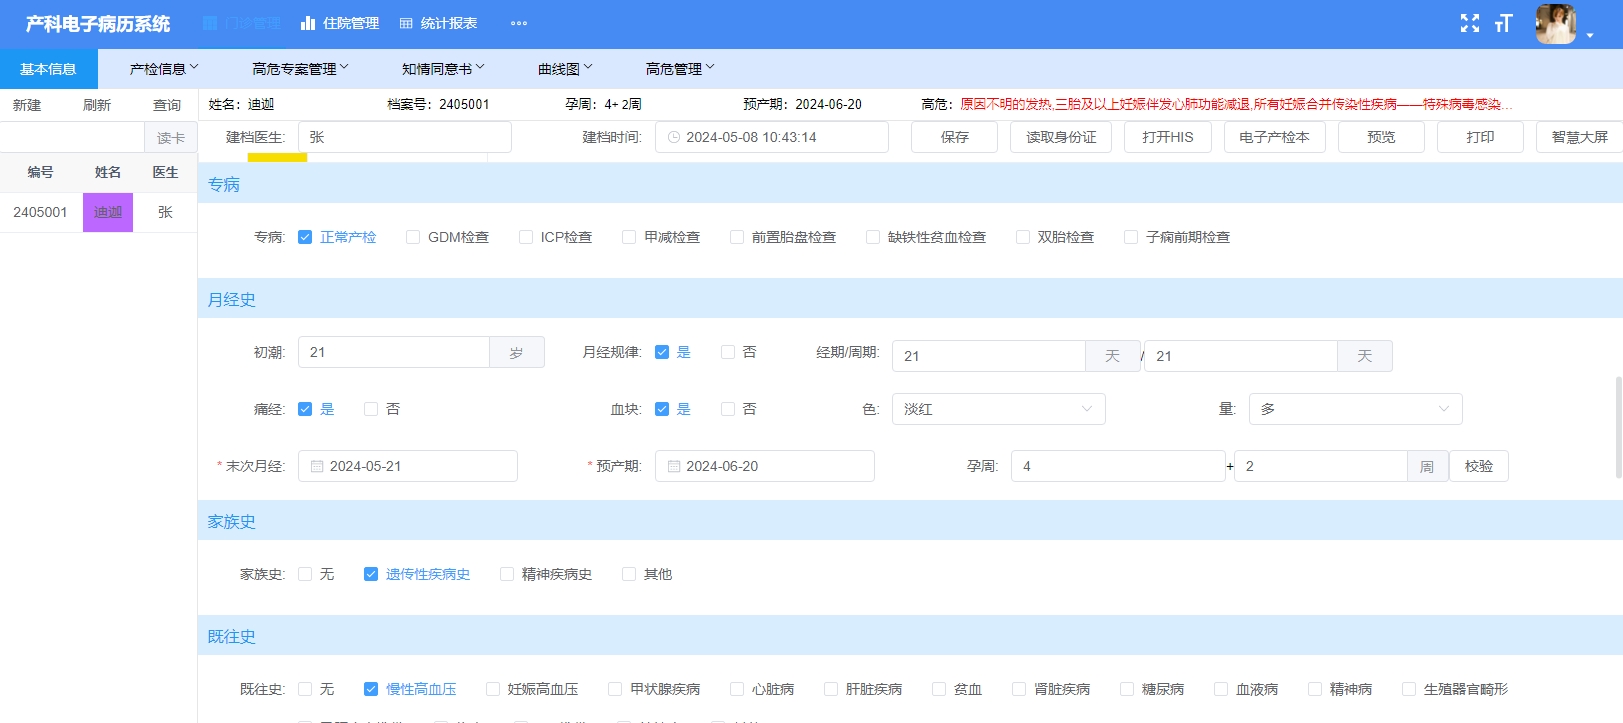

三、Java数字化产科管理平台源码 产科电子病历系统源码 智慧产科系统源码

数字化产科管理平台是为医院产科量身定制的信息管理系统。它管理了孕妇从怀孕开始到生产结束42天一系列医院保健服务信息。该系统由门诊系统、住院系统、数据统计模块三部分组成,与医院HIS、LIS、PACS、RIS等系统进行对接,完成数据的自动提取、集成和分析。集成孕妇门诊、住院和出院随访三个阶段信息,构建并打造出的一套完善的孕产妇保健信息化管理平台。

技术架构:前后端分离

开发语言:Java

开发工具:Idea,vscode

前端框架:Vue,ElementUI

数 据 库:MySQL8.0.36